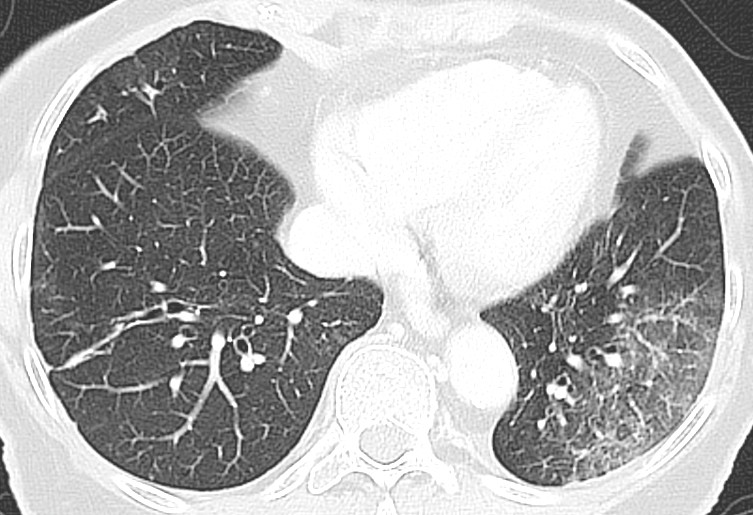

Typical CT findings vary with symptom duration and can be divided into three stages: an early phase, an intermediate phase that extends from 3–5 days after symptom onset, and a late phase.

There are not always CT findings the first few days after symptom onset. In a material with symptomatic, but unspecified patients, 56 % had normal CT findings within two days of symptom onset (12), declining to 9 % 3–5 days after symptom onset and 4 % 6–12 days after symptom onset. The frequency of findings varies with the severity of the disease. Initial diagnostic imaging yielded normal findings for 18 % in a cohort of patients who were not severely ill, but in only 3 % of patients who were (15). Typical CT findings are multiple, bilateral ground-glass opacities with peripheral distribution, most frequently located in the lower lobes. In the intermediate phase there are increasing amounts of consolidation and affection of several lobes, and increased septation with crazy paving as sign of interstitial affection. In the late phase there is increasing total extension, but ground-glass opacities and consolidation are still the dominant findings (12, 16). Figures 4, 5 and 6 show typical CT findings in different phases of COVID-19.

In a severe disease course, distortion of the lung architecture, traction bronchiectasis, enlarged lymph nodes and pleural fluid can be detected. These are findings that are not specific for COVID-19 (17).